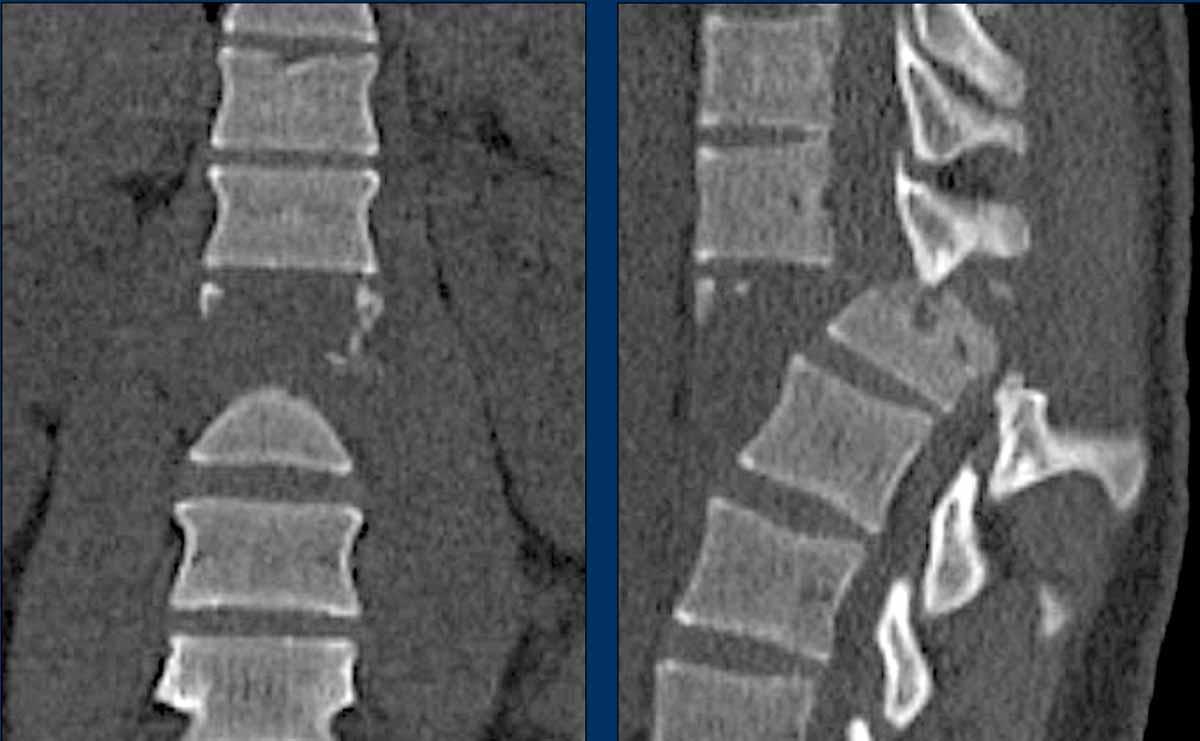

Images

Here we see a dislocation of the proximal levels to the right lateral side in the coronal plane.

Conclusion

Type C injury.